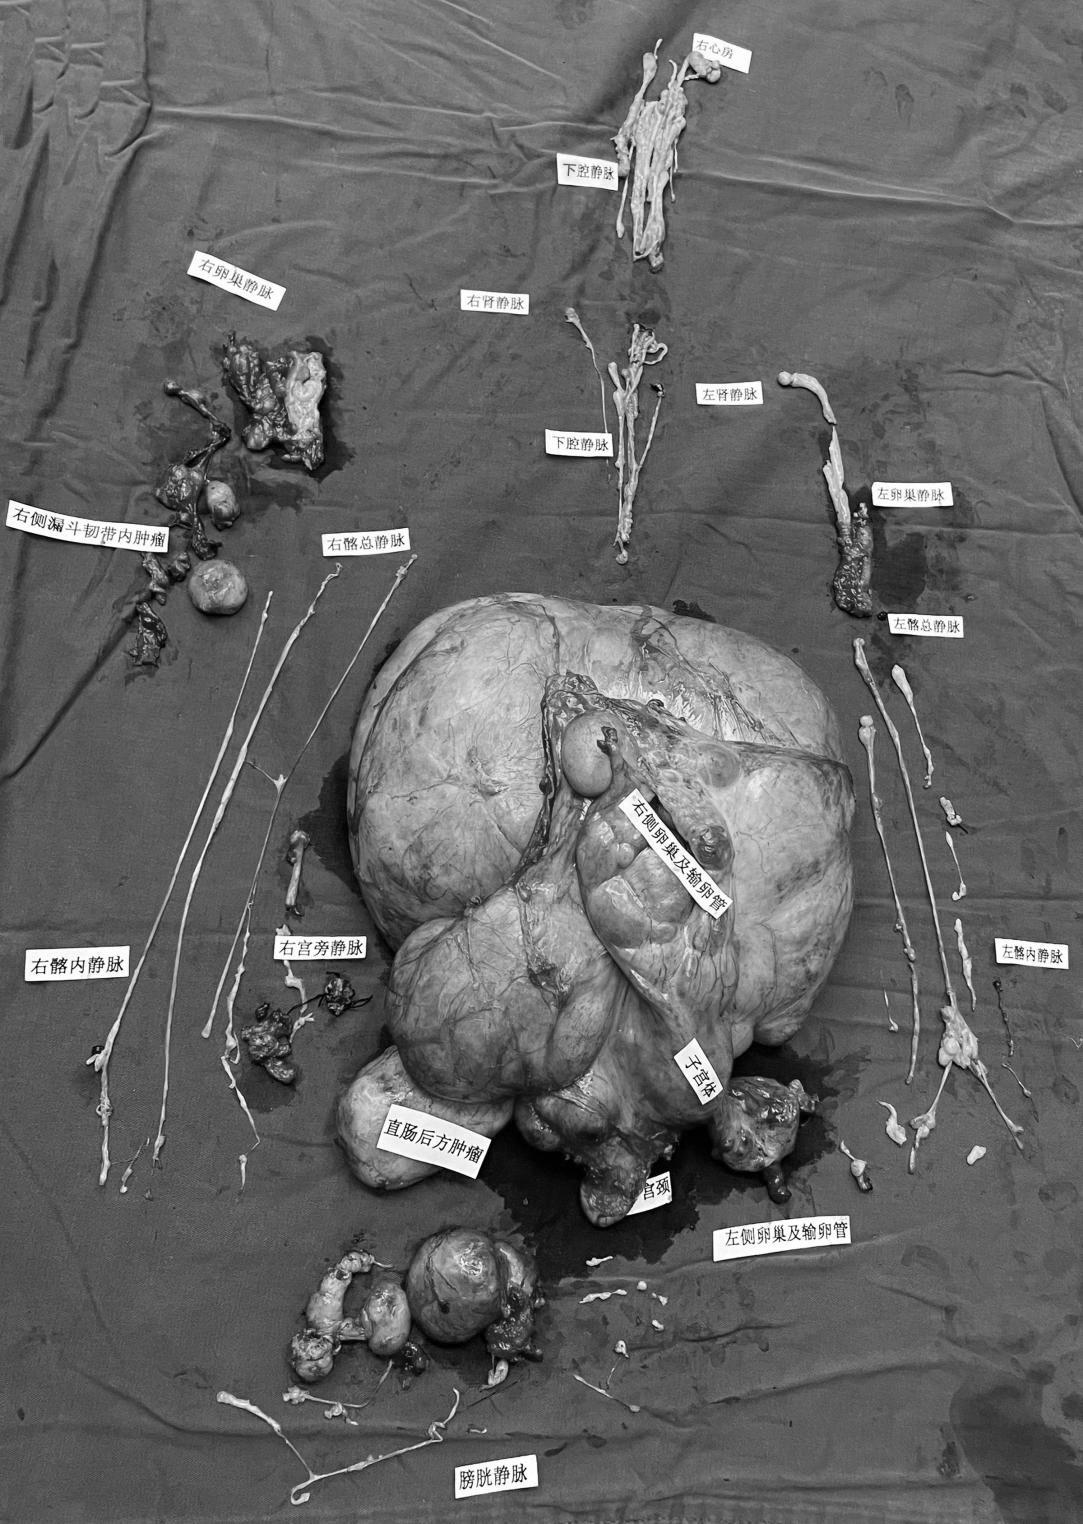

深圳的李女士身体里的“子宫肌瘤”从盆腔顺着静脉血管穿过腹腔和胸腔,一路“开疆拓土”,最终进入了右心房,严重危及她的生命。7月6日,深圳市人民医院妇科联合心脏大血管外科等14个科室,经过长达16个小时的“接力”手术,成功将李女士盆腹腔近9斤重的巨大肿瘤以及顺着血管一路蔓延生长至右心房的瘤体全部清除。此手术的成功彰显了深圳市人民医院的综合实力,标志着该院综合诊疗水平的“更上一层楼”。

医院综合超声、MRI、CT以及造影结果,基本确定李女士的肿瘤起源于子宫静脉系统,并由此沿着静脉血管一路蔓延而上,累及子宫、膀胱、下腔静脉、肾静脉、肝静脉。令医生更为惊奇的是,肿瘤还长进了李女士的右心房内。

马利国打开腹盆腔后,一颗巨大的肿瘤暴露在大家眼前,见过许多“大场面”的医务人员们还是被震惊了,这颗肿瘤位于腹膜后,几乎占满整个盆腹腔,肿瘤还与周边的膀胱、直肠等器官有不同程度的粘连。马利国联合脊柱外科主任杨大志、胃肠外科主任夏利刚及泌尿外科主任肖克峰充分探查腹盆腔情况,评估肌瘤与周边脏器及血管的位置,小心翼翼地将瘤体一点点完整剥离,切除下来的瘤体大小约35×25cm,重达9斤,超过一个巨大胎儿的重量(>4千克为巨大胎儿)。

这个“大家伙”切除后,接下来就是如藤蔓般蔓延到血管以及心脏的瘤体。按照原定方案,心脏大血管外科主任郑奇军开胸行体外循环,切开右心房取出在心脏及下腔静脉内的瘤栓。但在腹腔手术过程中,经食道超声监测提示,李女士心脏内的肿瘤被拖至心脏下方的下腔静脉中。这样一来,只需从下腔静脉入路,将肿瘤从血管拖拽出来,不必再对李女士进行体外循环和开胸手术,降低了患者手术风险及费用。

郑奇军仔细探查各处静脉血管,切开下腔静脉壁后,小心谨慎地将肿瘤拖了出来,取出的瘤体长达50cm。待其他血管内瘤体取出后,超声科的专家又对李女士进行了详细的超声探查,确认肿瘤已经被完全取出。